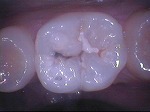

ドックスベストセメント

~ドックベストセメント処置~

~グラスアイオノマー仮封~

~CR充填~